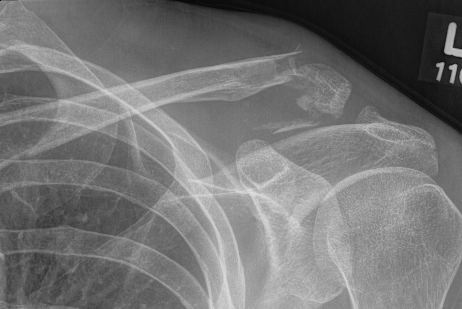

Compound clavicle fracture

Shorted / displaced midshaft clavicle fractures

Z shaped midshaft clavicle fracture